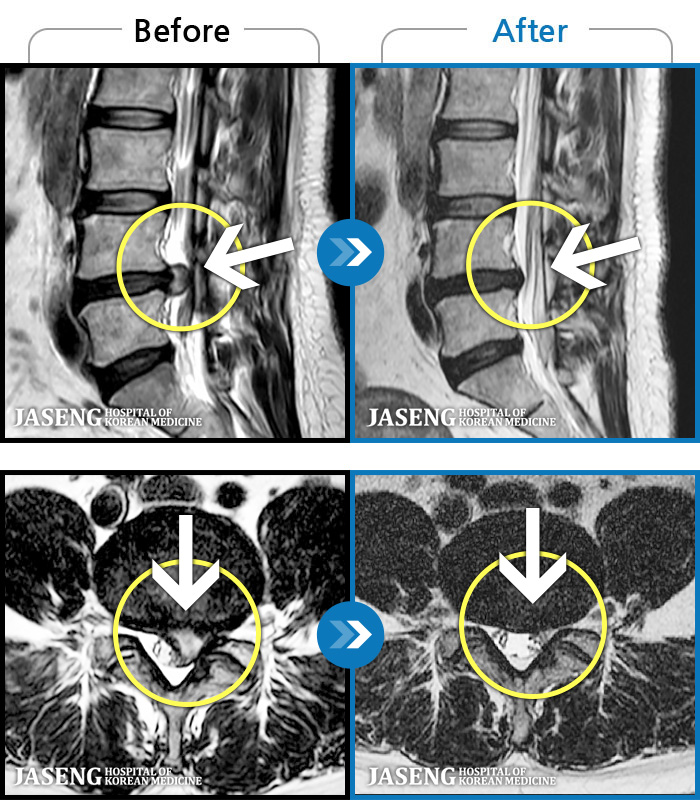

ȯںп Ǹ ǿ ԿǾ, ο ġ ۿ Ƿ ġḦ Ͻñ ٶϴ.